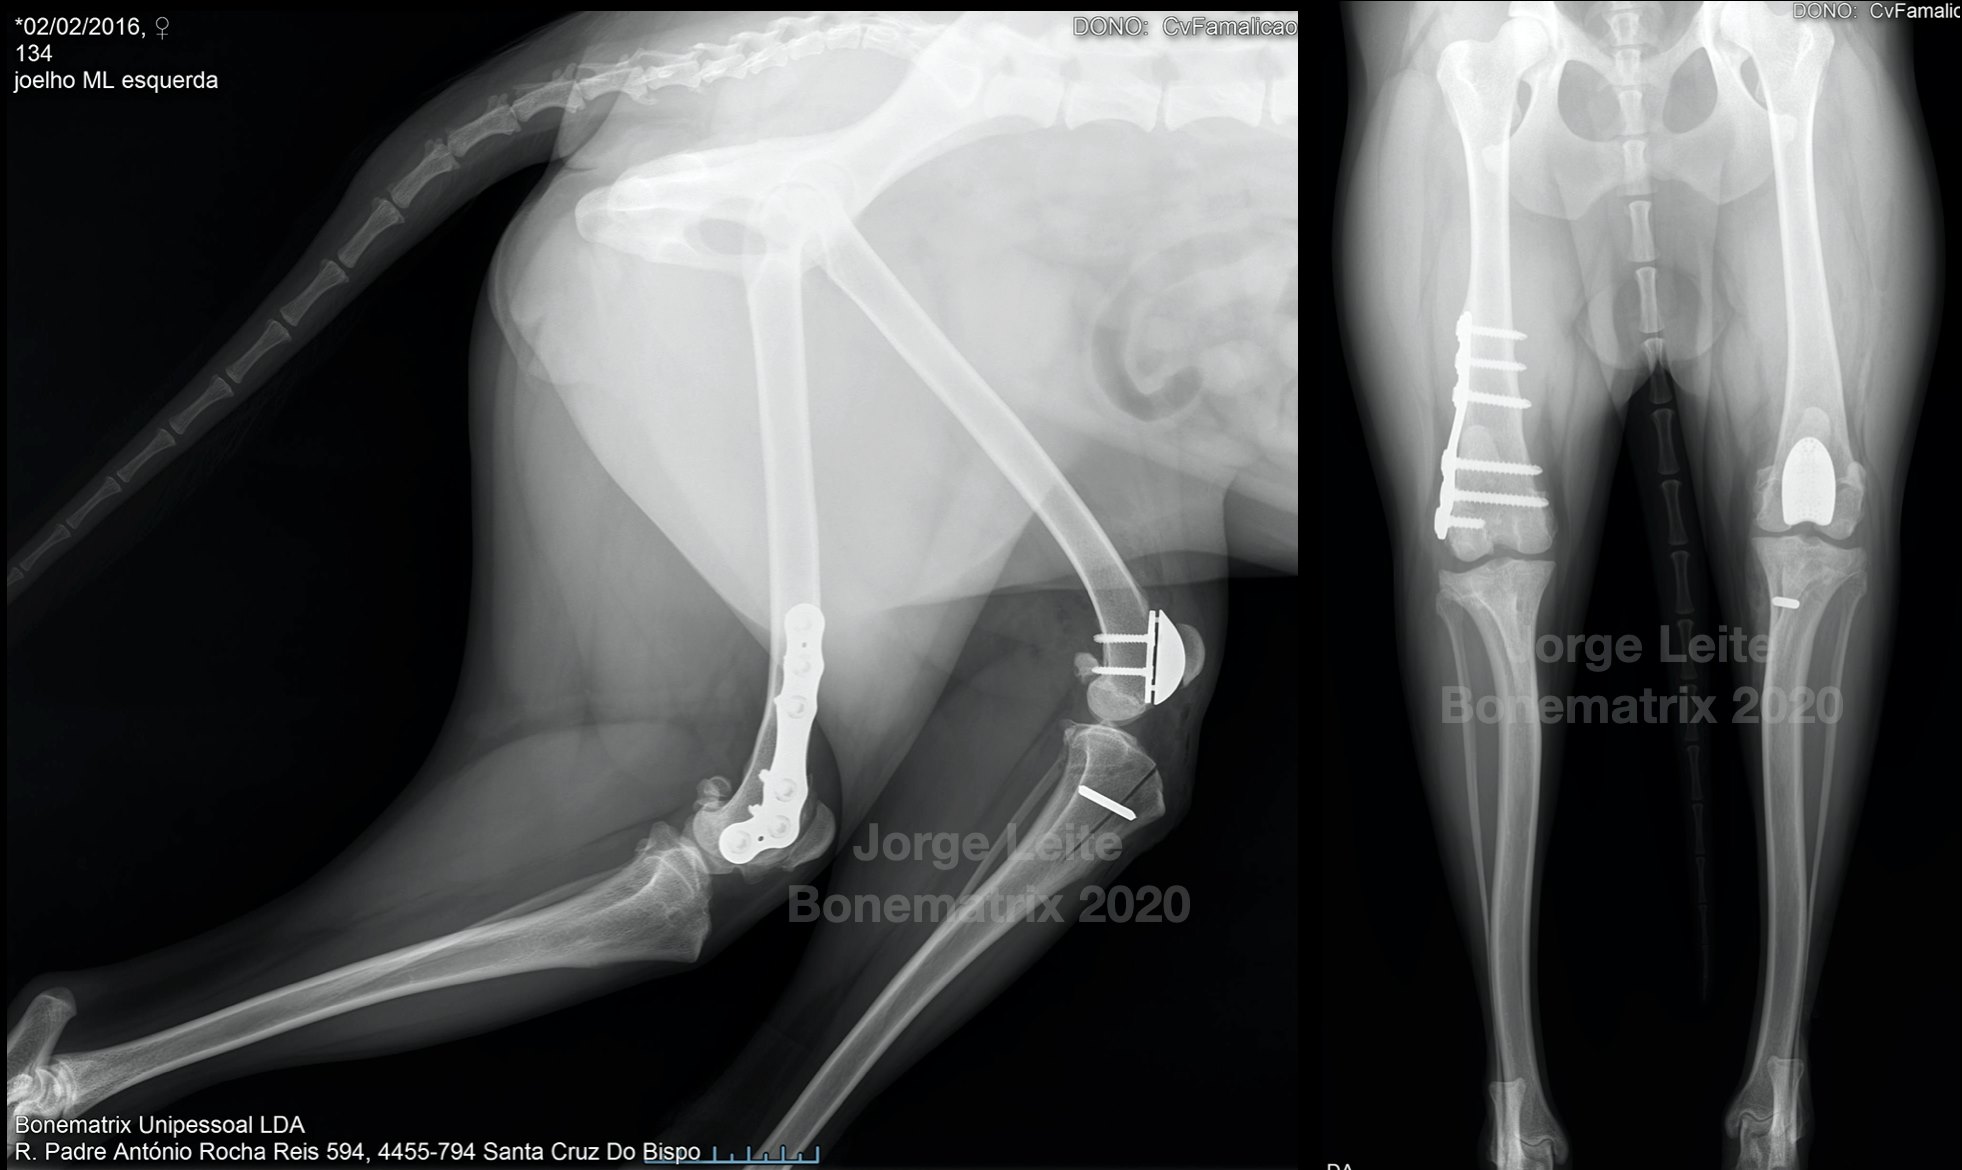

img